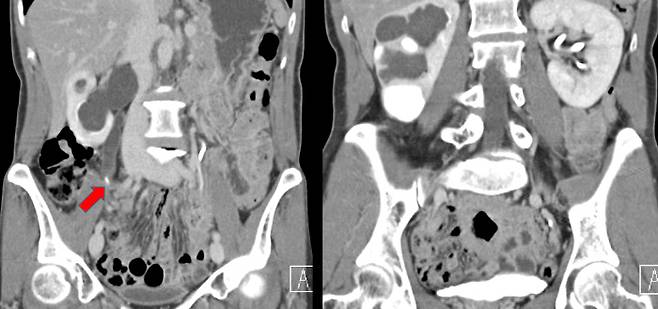

대표적인 합병증은 신장에 물이 차는 수신증이다. 요관에 결석이 생기면 소변이 나갈 수 없게 되면서 그 소변이 신장까지 차고 넘쳐 내부를 가득 메우고, 더 진행되면 내부 공간을 확장시킨다. 수신증이 발생하면 신장 기능이 떨어지고, 이 상태가 지속되면 신장 기능을 영구적으로 상실하며 만성신부전으로 이어질 수 있다.